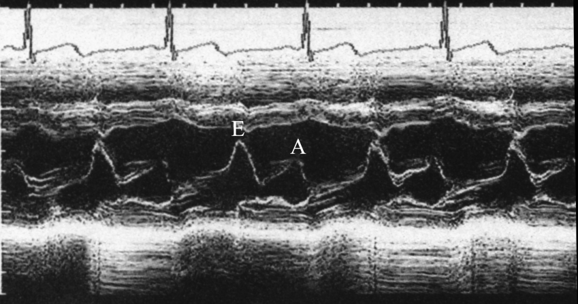

二、M型超声

A型基础上,沿时间展开